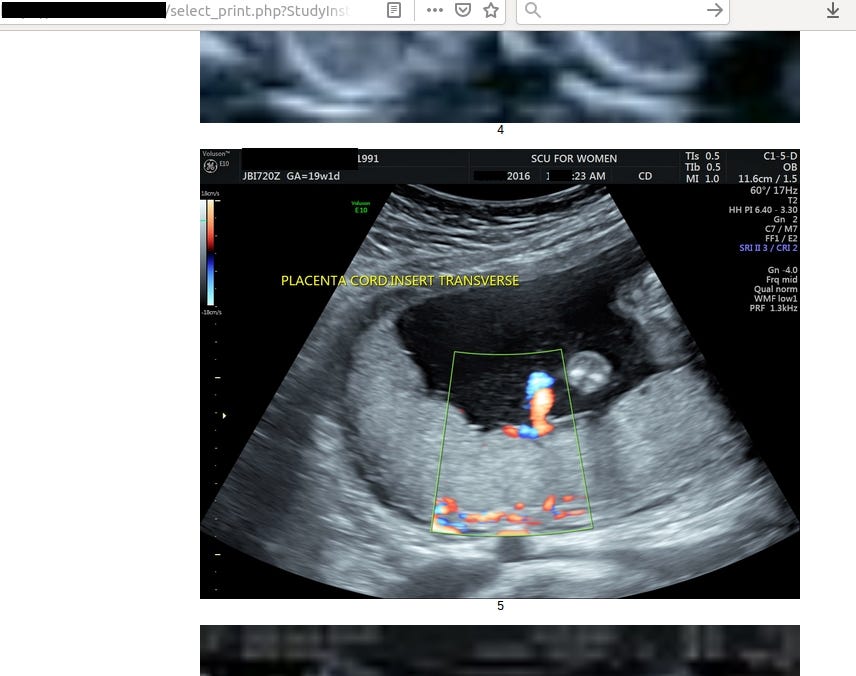

In this case leak contained 4,5 TB of data including radiology photos of pregnancies with diagnosis (almost 2M images!), invoices or personal patient’s data.

Going back to the main topic and the most important data in the leak, each patient has from 10 up to 40 radiology photos with description.

Frankly speaking, it says nothing for me but for someone acquainted with the topic it’s trove of information about health of patient and her fetus.